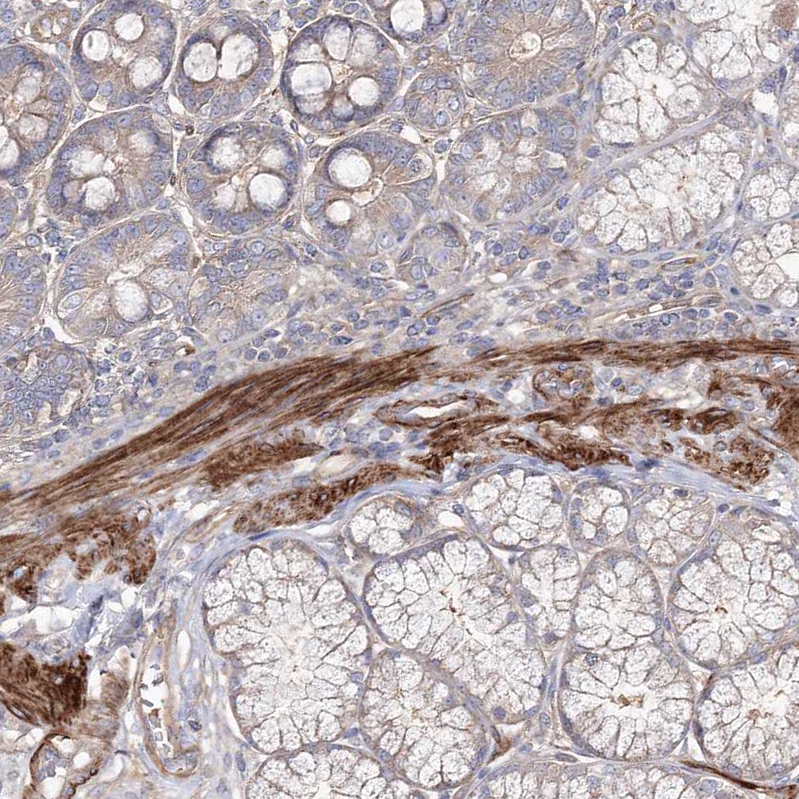

Immunohistochemical staining of human duodenum shows strong cytoplasmic positivity in smooth muscle cells.